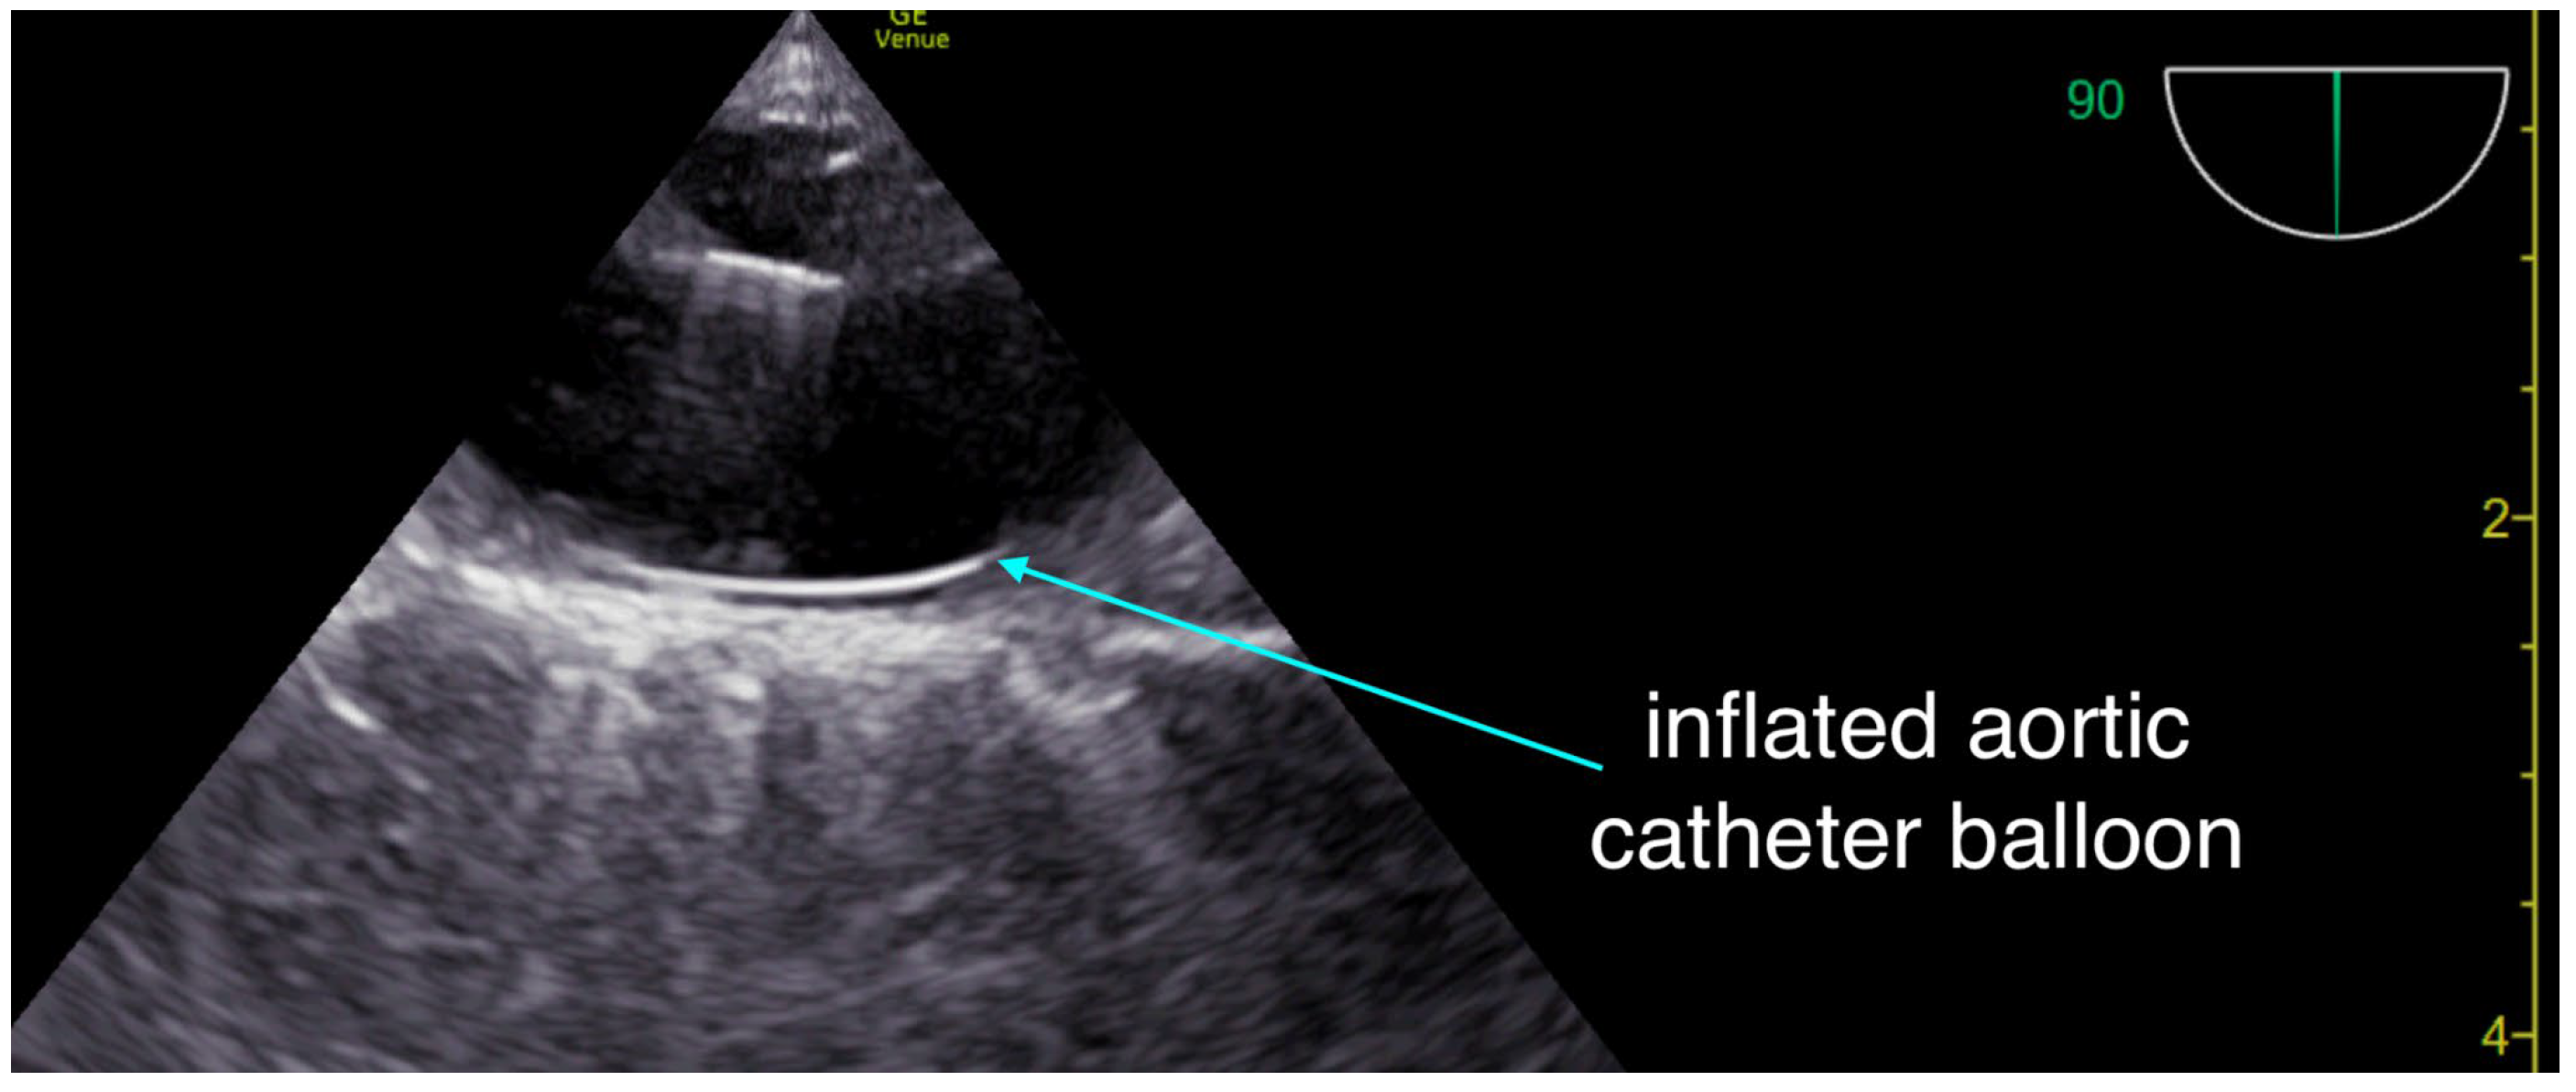

During CPR, transcranial Doppler (TCD) was used to assess intracranial flow. (Figure 1) It revealed a systolic upstroke but also early diastolic flow reversal and no significant forward flow during the remainder of diastole, which was thought to reflect severely impaired cerebral perfusion, either from markedly vasoconstricted intracerebral arterioles secondary to epinephrine administration or from elevated intracranial pressure.

During transport, hemodynamics were continuously monitored using resuscitative TEE. The epinephrine infusion was continued. End-tidal CO2 remained at greater than 40 mmHg, and arterial blood pressure stayed above 100 mmHg systolic. However, pulse pressure was narrow, with diastolic pressures generally ranging between 70 and 90 mmHg.Upon arrival at the tertiary care center, the patient was assessed by the treating team. The Glasgow Coma Scale was 3, pupils were minimally reactive, and no gag reflex was present. Repeat transcranial Doppler demonstrated the same pattern of systolic flow with early diastolic flow reversal and an absence of forward flow during the remainder of diastole.

Transcranial Doppler provides a window into intracranial hemodynamics, arguably the most important determinant of outcome during cardiac arrest resuscitation. In this case, the absence of diastolic forward flow with early diastolic flow reversal (Figure 1) was interpreted as either excessive vasoconstriction of intracerebral arterioles impairing perfusion, or significant cerebral edema causing elevated intracranial pressure (ICP). Optic nerve sheath ultrasound could have helped differentiate between these two mechanisms, but was not performed. Given the very limited literature, these observations remain theoretical and warrant further study, as we currently lack tools to tailor resuscitative strategies directly to cerebral flow.

Figure 1. Intra-arrest trans-cranial Doppler during mechanical chest compressions showing antegrade systolic flow and retrograde diastolic flow reversal.